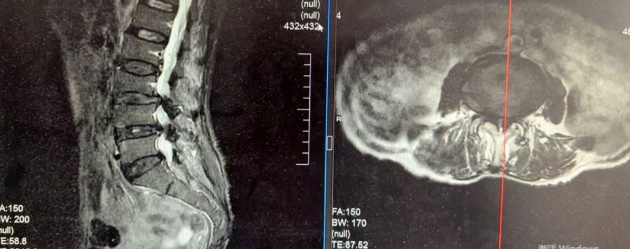

77岁的宋奶奶,因腰椎管狭窄、椎间盘突出,双下肢剧烈疼痛、麻木无力,不仅无法独立行走,连夜间睡觉都无法平卧,生活质量极差。

更棘手的是,她还患有严重的心脏瓣膜病、心律失常等基础病,身体耐受性差。传统开放手术创伤大、风险高,保守治疗又效果甚微,治疗一度陷入困境。